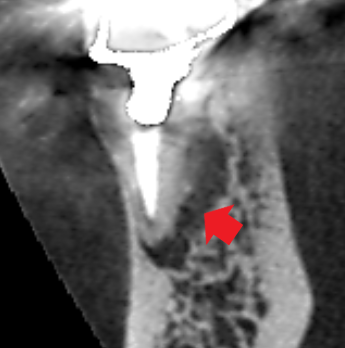

初診時の下顎第一大臼歯の矢状断のCT画像です。

矢印の先に膿の影がみられます。